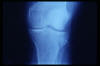

APR Gonartrosis